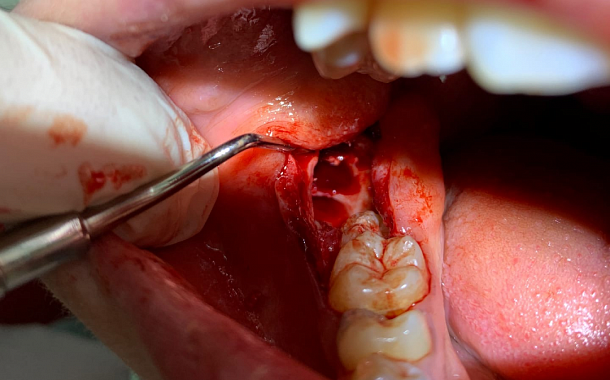

В стандартном случае этапы удаления зуба выглядят так:

1. Анестезия или погружение в «сон».

2. Атравматичное удаление корня с минимальной травмой костных структур лунки корня.

3. Антисептическая обработка костной раны, кюретаж грануляций или удаление оболочки кистозной полости, то есть удаление из лунки тканей, поддерживающих воспалительный процесс и препятствующих правильному заживлению лунки.

4. Заполнение лунки костно-пластическим материалом BioOss, закрытие зоны подсадки костной ткани, входа в лунку мембраной богатой тромбоцитами - APRF.

5. Ушивание лунки.

3. Атравматичное удаление зуба: его разделяют на несколько фрагментов, чтобы уменьшить объем иссечения кости вокруг коронки неправильно расположенного зуба и тем самым минимизировать риск травмы расположенных рядом анатомических образований.

4. Антисептическая обработка костной раны и заполнение лунки мембраной богатой тромбоцитами - APRF.